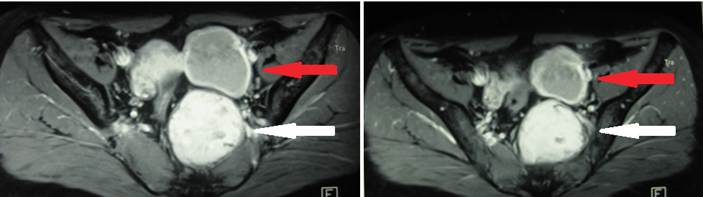

En el postoperatorio se solicitó una tomografía computarizada que informó la “presencia de una lesión sólida localizada a nivel presacro, de 58 x 50 x 48 mm, adyacente a la cara izquierda del recto, que lo deforma y a la vez ensancha el agujero de conjunción sacro. La tumoración presenta bordes bien definidos con captación de contraste, sugestivo de tumor de extirpe neurogénico. Además, presencia de una tumoración quística a nivel de ovario izquierdo de 55 x 50 mm” (Figura 1).

La paciente fue atendida y hospitalizada en el Hospital Nacional Edgardo Rebagliati Martins - EsSalud, Lima, Perú, debido al incremento paulatino de la intensidad de los síntomas, y se realizaron los estudios complementarios. El tacto rectal y la colonoscopía no encontraron hallazgos significativos. La resonancia magnética informó “una lesión sólida ovoidea en región presacra de 65 x 50 mm, que remodela el sacro por contacto directo, no es de origen óseo y se localiza a nivel de la tercera vértebra sacra. Además, describía la presencia de una lesión quística anexial izquierda de 55 x 45 mm” (Figura 2). La ecografía transvaginal evidenció una masa sólida heterogénea retrorrectal o presacra, que medía 65 x 55 x 48 mm.

Las técnicas de imagen más utilizadas son la tomografía computarizada y la resonancia magnética, que confirman el diagnóstico de un tumor retrorrectal, sugieren el diagnóstico de Schwannoma, y sirven para planificar la técnica quirúrgica. La tomografía computarizada de la pelvis puede identificar tumores pequeños, distinguir una lesión quística de una lesión sólida y revelar el compromiso sacro o invasión de estructuras adyacentes, como en esta paciente.

La resonancia magnética de pelvis es particularmente útil para delinear planos de tejidos blandos, delimitar claramente la presencia de una cápsula y evaluar la presencia o ausencia de invasión ósea y afectación nerviosa, por lo que se constituye en el procedimiento diagnóstico de elección para este tipo de tumores 7,10. La diferenciación entre Schwannomas benignos y malignos, así como entre Schwannomas y otros tumores de tejidos blandos, como fibrosarcomas y liposarcomas, constituyen un desafío debido a la falta de características distintivas 4.